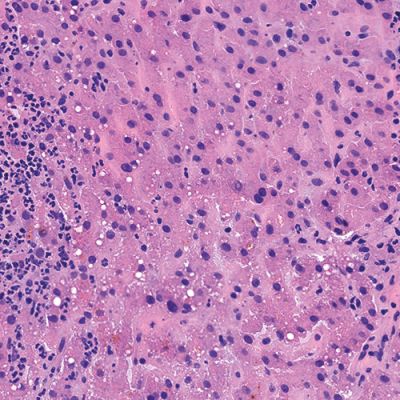

High Quality Results

Pathologists rely heavily on the frozen section technique for intra-operative consultation when the surgeon requires a rapid diagnosis or immediate feedback regarding surgical margins. Frozen sections offer a short turnaround time (15-20 minutes) but usually have the disadvantage of lower diagnostic quality than paraffin sections due to cryoembedding artifacts and variability in staining protocols.

Milestone offers a new approach to overcome these limitations by combining the artifact-free freezing process of PrestoCHILL with the superior processing and staining capabilities of PRESTO PRO.

The advantage of PRESTO PRO is that it provides a standardized and reproducible process that is capable of both efficient processing and staining protocols. This results in improved morphology of the analyzed specimens and maintains a high standard of result quality.